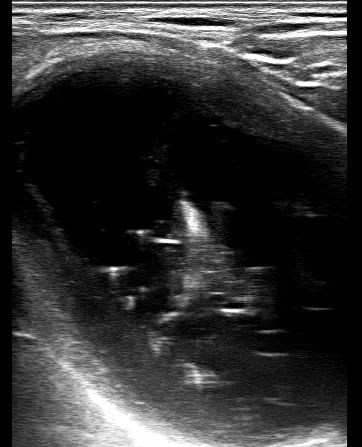

7月12日,明先生来到嘉定区中心医院就诊,超声结果显示,甲状腺左叶可见一直径7cm的结节,并且向胸骨后方延伸。CT结果显示上纵膈占位,气管局部受压移位变形,局部管腔变窄。喉镜结果显示右侧声带麻痹。结合病史及影像资料,考虑甲状腺结节压迫喉返神经导致声音嘶哑。